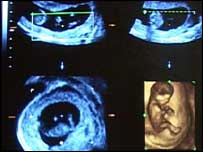

Imagem de feto capturada por meio de ultra-som

Foram mostradas também imagens de fetos abortados em diferentes períodos, de sete a 21 semanas de gravidez.